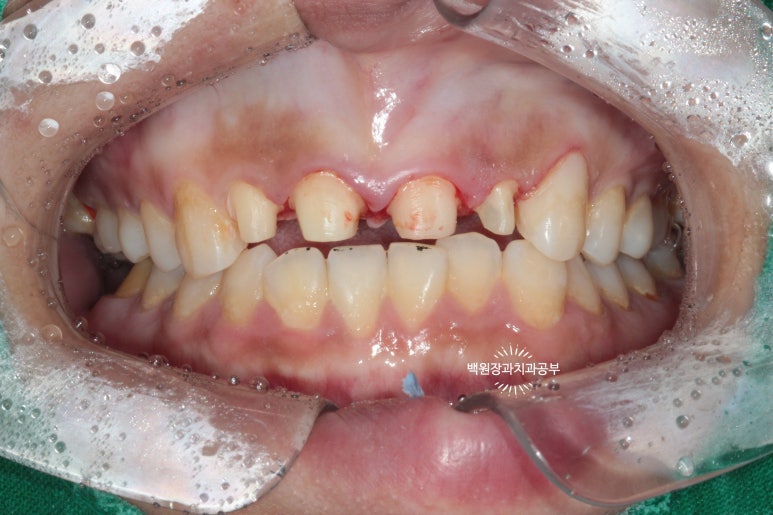

저희 병원을 처음 내원하셨을 때의 구내 임상사진입니다.

20대 여성분이셨는데, 개인 사정으로 적절한 내원 타이밍을 놓쳐 대문니(=중절치)를 비롯하여 상당히 충치가 진행된 양상을 띄고 있습니다. 특히 대문이 옆의 작은 앞니(=측절치)는 충치가 더 심했습니다.

고개를 살짝 돌려 찍어본 사진에서 더 확연히 치아우식증( =충치)을 확인 할 수 있습니다.

딱 보기에도 치료가 아주 시급해 보이는 상황이었어요!!

그리고 화살표로 표시한 양쪽 작은 앞니는 왜소치로 그 크기가 2/3 정도로 작은 소견을 보실 수 있습니다.

환자분은 당시에 흡연 하시는 상태였는데요, 그로 인해 치은염 (=잇몸 염증)도 심하여 꽤나 잇몸이 부어있는 것을 확인할 수 있었습니다.

화살표로 표시해 둔 치아와 치아 사이의 잇몸이 상당히 붉고, 붓기로 인해 모양이 둥그렇게 변한 것을 보실 수 있습니다. 전형적인 치은염/치주염 소견입니다. 심해지면 풍치가 됩니다.